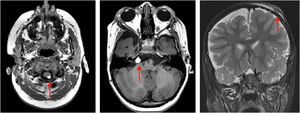

On physical examination, a heterogeneous alopecic plaque was identified on the scalp, located in the vertex region, with areas of atrophy and others with a softened consistency, similar to adipose tissue, with a clinical appearance compatible with nevus psiloliparus (Fig. 1). The histopathology of one portion of the lesion was suggestive of aplasia cutis. The presence of freckles in the axillary region ipsilateral to the ocular and neurological findings was also observed (Fig. 2). Other anomalies, such as craniosynostosis of the sagittal suture, short stature, low hairline in a "V" shape in the posterior cervical region, low-set right ear with a folded helix, thin lips with eversion of the upper lip, and overlapping fingers, compatible with clinodactyly, were also evidenced. Magnetic resonance imaging (MRI) revealed multiple intracranial lipomas, as well as thickening of the tissue corresponding clinically to the area of alopecia (Fig. 3) in the right frontoparietal region. Based on the clinical picture, histopathological findings, and MRI results, a diagnosis of ECCL was made.